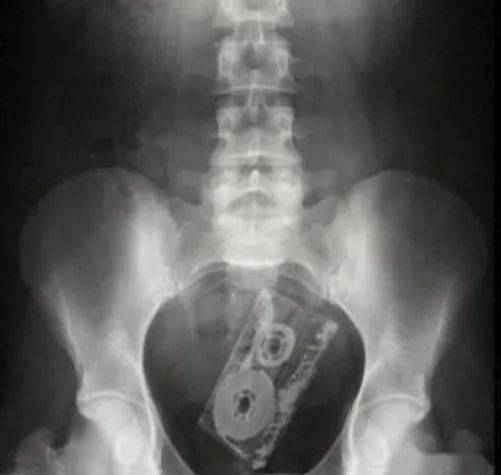

▷磁带